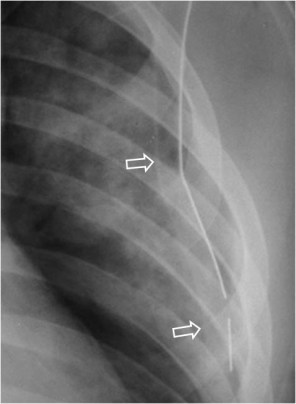

SIGNO DEL BORDE INCOMPLETO

Otro signo que define a las lesiones extrapleurales es que presentan un margen visible (el que está en contacto con el pulmón adyacente) y un margen no visible (en contacto con la pared torácica). Por ello, el borde completo de la lesión no es del todo visible. En la imagen de la izquierda vemos una lesión extrapleural apical derecha correspondiente a un neurofibroma en un paciente con neurofibromatosis. A la derecha, un tumor fibroso pleural benigno en la base izquierda.